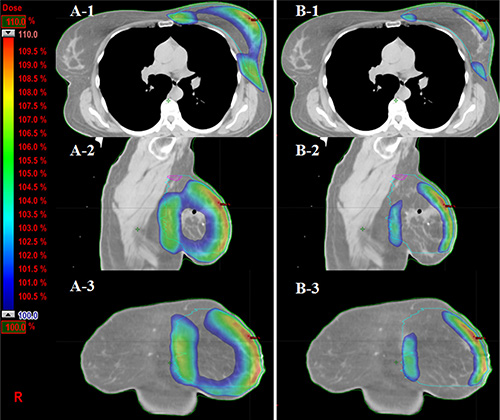

Figure 2: Comparison of skin volumes received more than 100% prescription dose (PD) in three views. (A-1, 2, 3) The skin volumes received more than 100% PD from axial, sagittal and coronal views in 3DCRT plan from one patient. (B-1, 2, 3) The volume of corresponding dose in eComp plan is much smaller than those in 3DCRT plan.